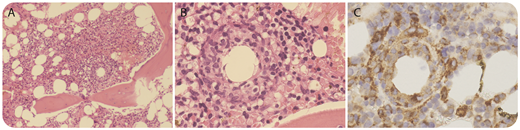

A 53-year-old woman presented with fever, chills, and rigors associated with occipital headache with no localizing sign or symptoms. She had recently returned to Australia after spending 2 months in Cambodia. C-reactive protein level peaked at 120 mg/L. Initial extensive microbe cultures were negative. A whole-body computed tomography scan did not detect any infection or malignancy. As part of the work-up for fever of unknown origin, a bone marrow biopsy was performed. Her bone marrow aspirate was hypercellular with increased granulopoiesis that was left shifted. Careful examination of the trephine sample showed occasional noncaseating ring-shaped granulomas (panel A, original magnification ×10; panel B, original magnification ×40; hematoxylin and eosin stain). Monocytes and histiocytes were diffusely increased and surrounded the granulomas (panel C, original magnification ×40; CD68 immunohistochemical stain). A sample with Ziehl-Neelsen stain was negative and there was no malignant infiltration. Although epithelioid/ring granulomas are characteristic of Q fever, they are not pathognomonic of Q fever and have been reported in patients with viral infections, brucellosis, leishmaniasis, and lymphomas. Q fever serology demonstrated seroconversion consistent with recent infection.

Q fever is the result of an infection by Coxiella burnetii, a gram-negative intracellular bacteria, and patients usually present with protracted severe flu-like symptoms. Our patient was started on treatment with doxycycline, which resulted in resolution of her symptoms.